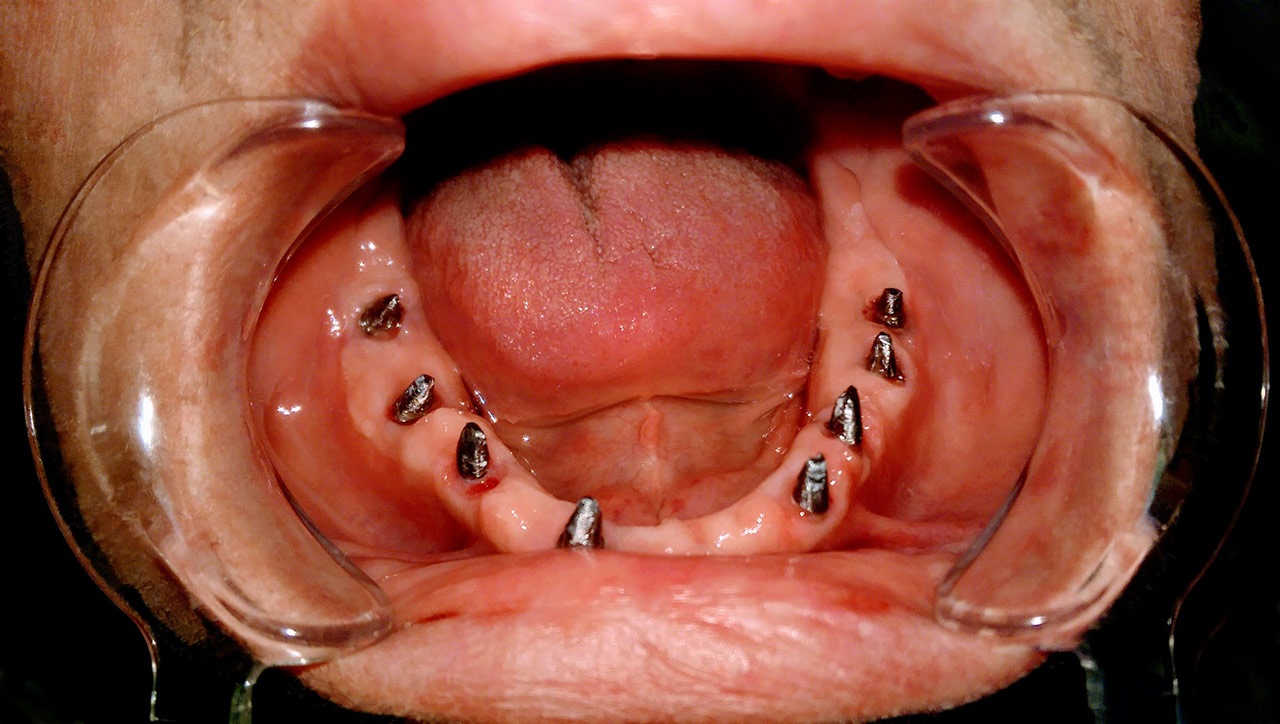

Teljes fogatlanság helyreállítása 2 nap alatt

Teljes fogatlanság helyreállítása 2 nap alatt azonnal terhelhető svájci IHDE implantátumokkal és PMMA műanyag hidakkal. Intraorális szkennerrel vettünk lenyomatot az implantáció után, és erre a digitális mintára készítette el a fogtechnika a hidak digitális tervezését, majd faragta ki műanyagból. Ezt a gyors munkát az azonnal terhelhető implantátumok és a digitális lenyomat, tervezés segítségével tudtuk megcsinálni mindössze 2 nap alatt. Dr. Kelemen Péter és a Symbion Fogtechnika munkája.